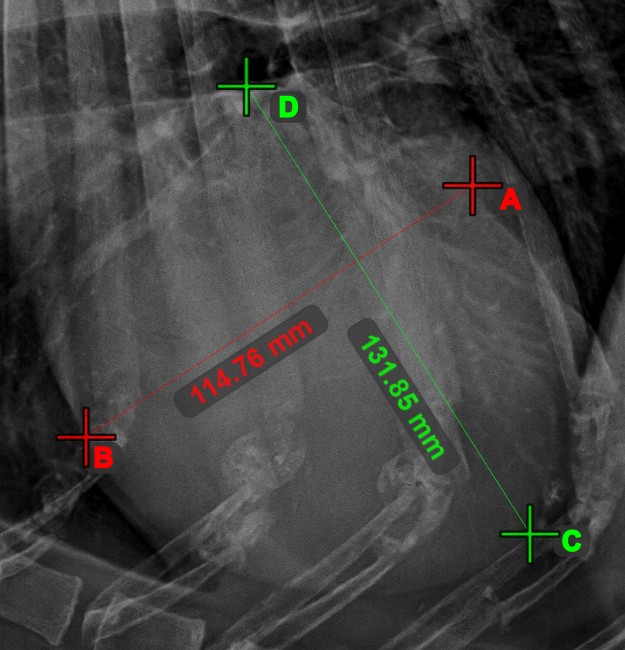

Create a line measurement to calculate the distance between two points with high precision.

Select the Line Measurement tool and assign it to one of the available mouse buttons. Place the start and end points on the scene or select them from already existing points on the image. The distance between the two points will be automatically calculated by using the default calibration data, or the recalibrated data by the length calibration measurement.

Modify the start and end point by using the Select/Move Item tool. The distance between the two points will be automatically recalculated.

../_images/image164.jpg